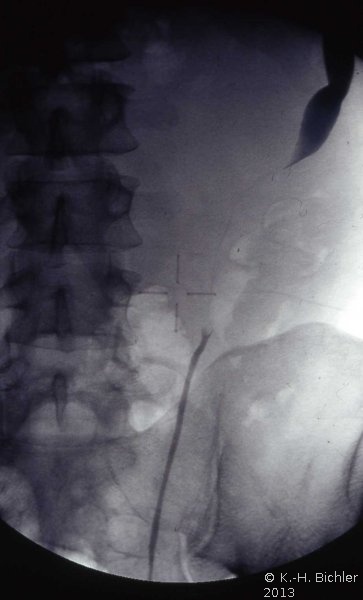

Die Röntgenübersicht der Niere und ableitenden Harnwege zeigten keinen Anhalt für Konkrement. Im Ausscheidungsurogramm eine "stumme Niere" links (Abbildung 19a). Bei der retrograden Sondierung links fand sich keine Abflussbehinderung (Stein oder Stenose) (Abbildung 19c). Im MCU kein Anhalt für Reflux (Abbildung 19b). Im Nierenfunktionsszintigramm MAG3 wurde eine seitengetrennte Funktionsverteilung von rechts zu links wie 93% zu 7% festgestellt. Zur Abklärung eventueller Gefäßalterationen erfolgte eine Renovasographie mit dem Nachweis einer langstreckigen Stenose der linken Arteria renalis (Abbildung 19d). Wegen des Verdachtes auf eine generalisierte Arteriitis wurden Angiographien weiterer Gefäßgebiete durchgeführt: Dabei fanden sich eine geringgradige Einengung der infrarenalen Aorta und der linken Arteria subclavia.